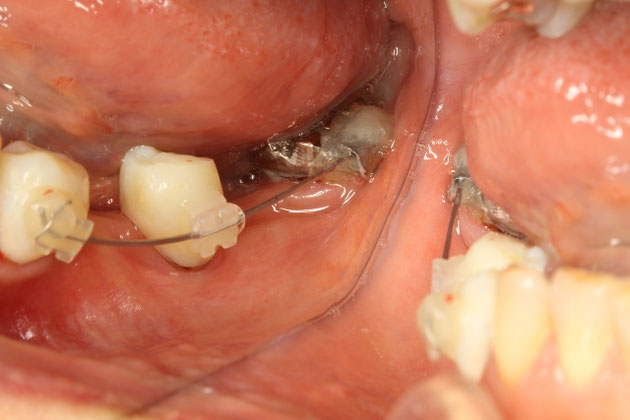

写真のように、歯茎の粘膜と呼ばれている移動する歯茎が歯の近くまであると、歯茎が炎症を起こしやすく、また、頬が歯に近くなりすぎるために物が詰まりやすくなってしまったり、歯磨きをしにくくなります.

このケースでは、角化した歯茎を移植する事で歯茎を強化し、歯ブラシがしやすい状態にします.